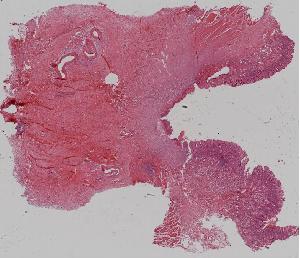

27. Squamous cell carcinoma of the esophagus